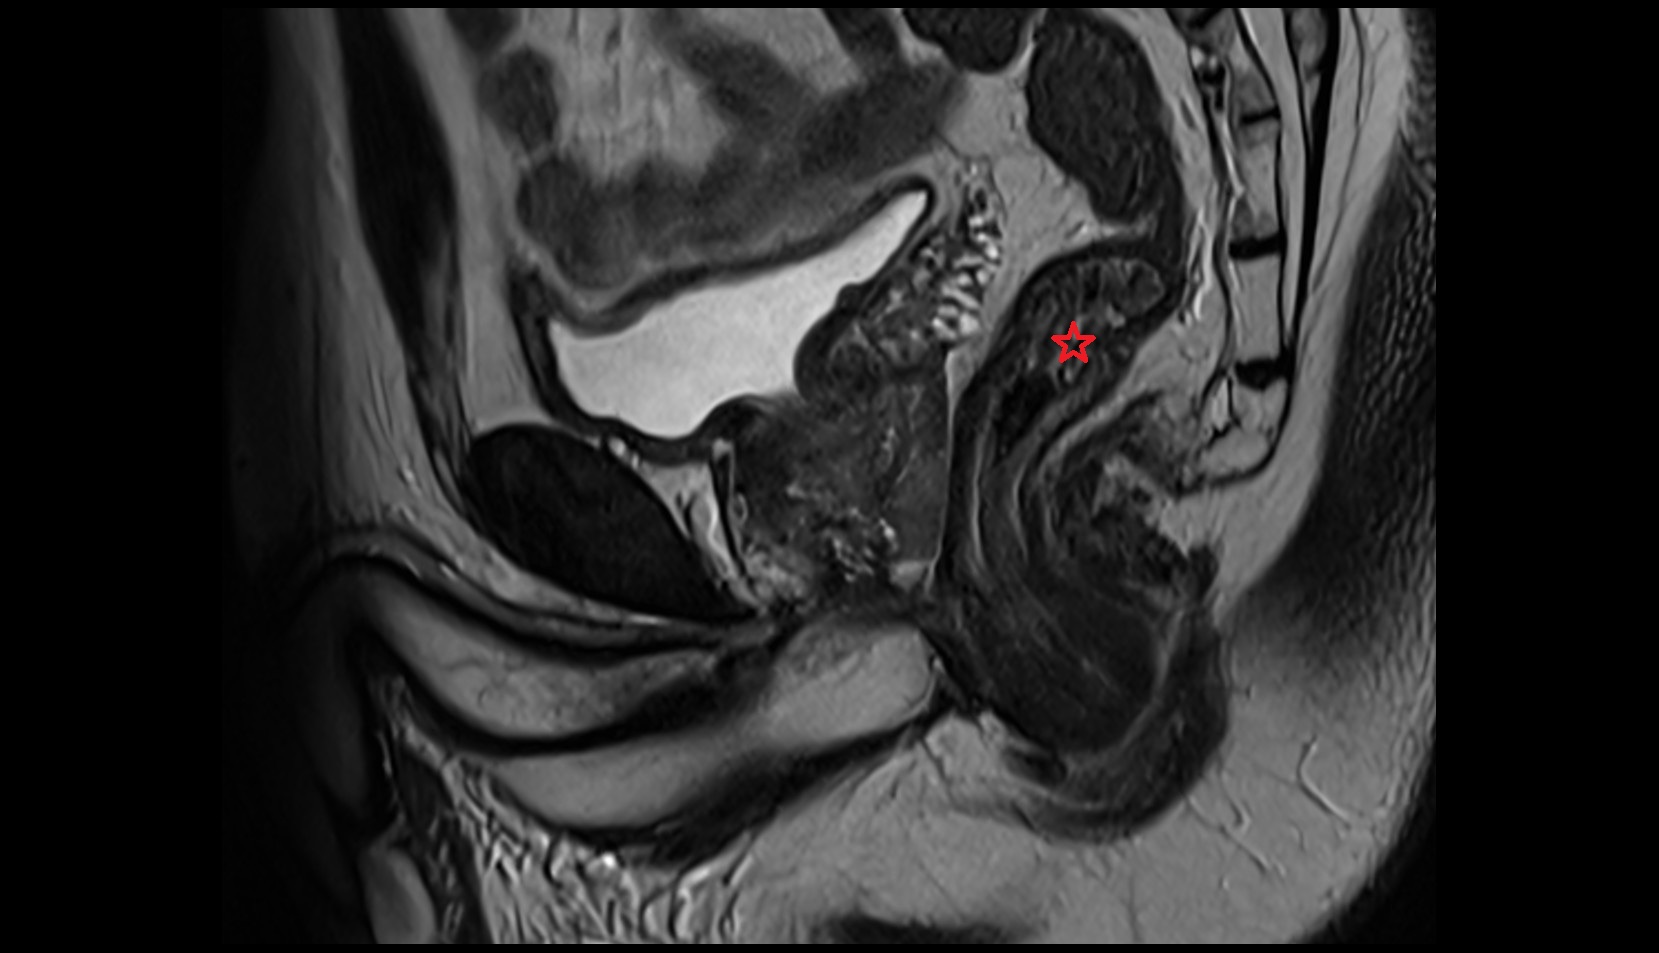

- Uterus

- Body of uterus

- Fundus of uterus

- Cervix of uterus

- Isthmus of uterus

- Vagina

- Endometrium of uterus

- Myometrium of uterus

- Perimetrium of uterus

- Junctional zone of uterus

- Ovaries

- Fallopian tube

- Broad ligament of uterus

- Vesicouterine pouch

- Rectouterine pouch (pouch of Douglas)